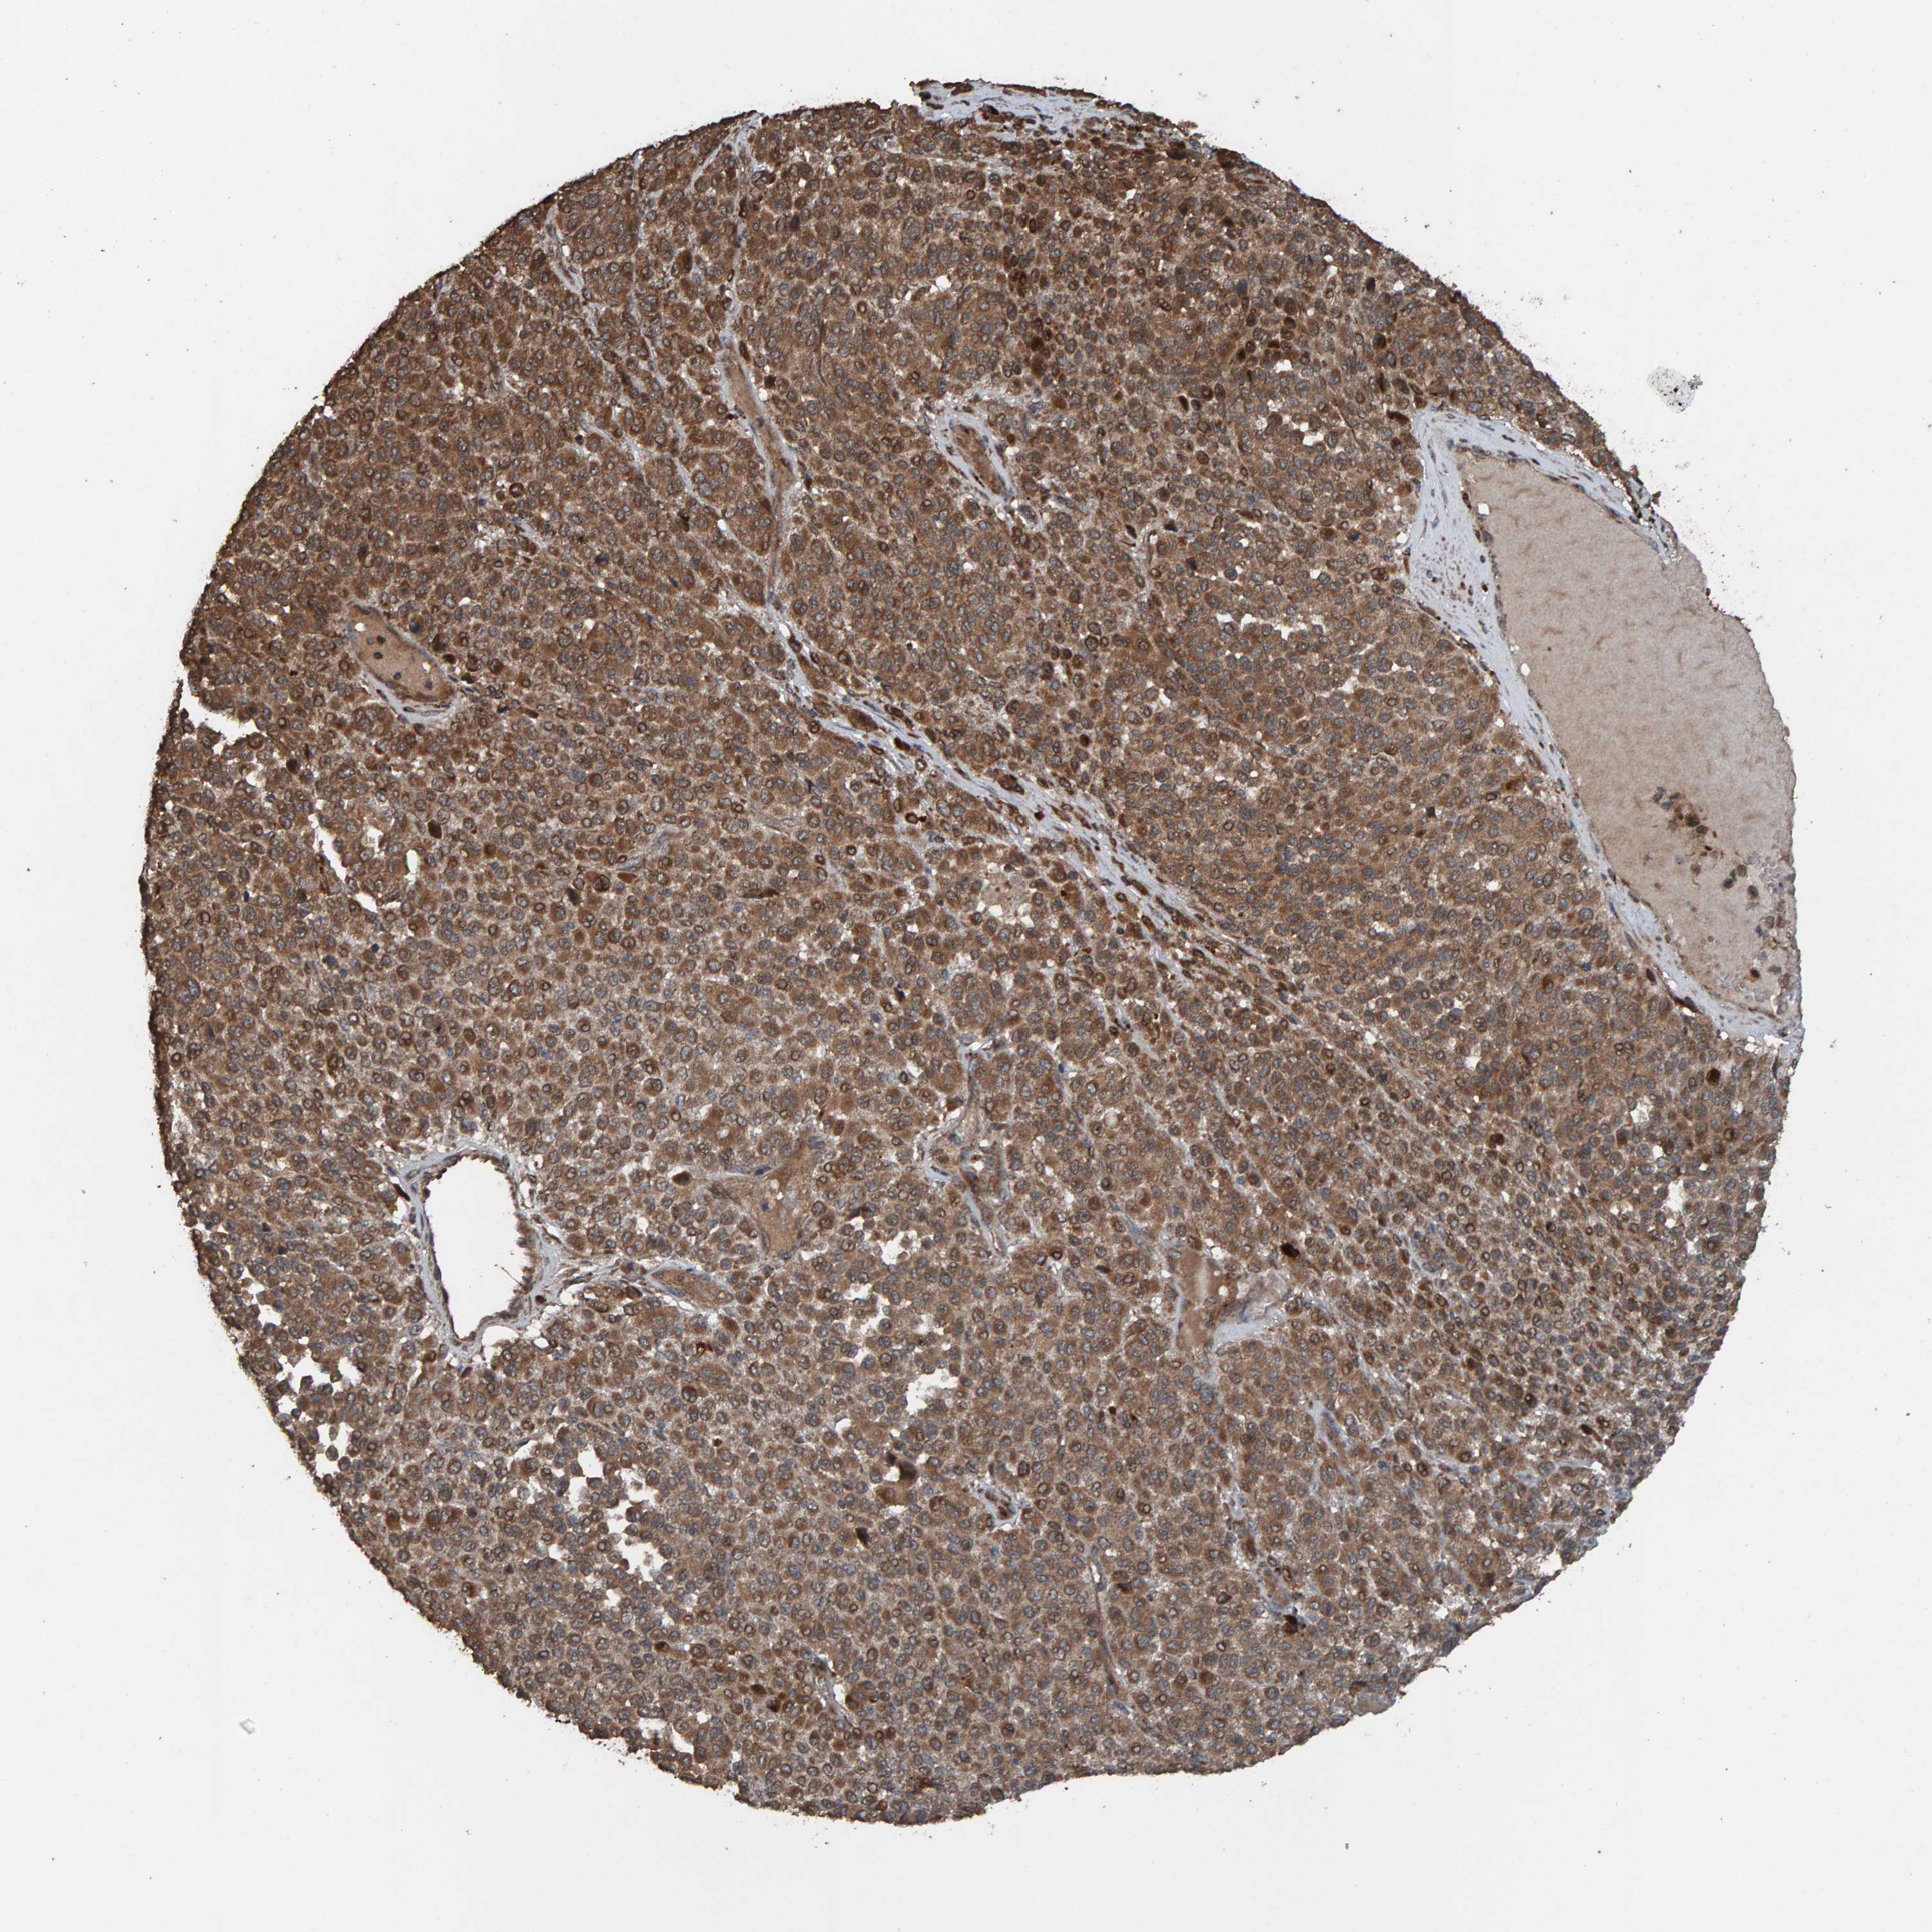

MELANOMA - Protein expressioni

A mouse-over function shows sample information and annotation data. Click on an image to view it in a full screen mode. Samples can be filtered based on level of antibody staining by selecting one or several of the following categories: high, medium, low and not detected. The assay and annotation is described here.

Note that samples used for immunohistochemistry by the Human Protein Atlas do not correspond to samples in the TCGA dataset.

Antibody stainingi

Antibody staining in the annotated cell types in the current human tissue is reported as not detected, low, medium, or high, based on conventional immunohistochemistry profiling in selected tissues. This score is based on the combination of the staining intensity and fraction of stained cells.

Each image is clickable and will lead to virtual microscopy that enables deeper exploration of all samples and also displays staining intensity scores, fraction scores and subcellular localization as well as patient and tissue information for each sample.

Antibody HPA023384

Staining

High

Medium

Low

Not detected

Intensity

Strong

Moderate

Weak

Negative

Quantity

>75%

75%-25%

<25%

None

Location

Nuclear

Cytoplasmic/membranous

Cytoplasmic/membranous,nuclear

Malignant melanoma, NOS

Malignant melanoma, Metastatic site